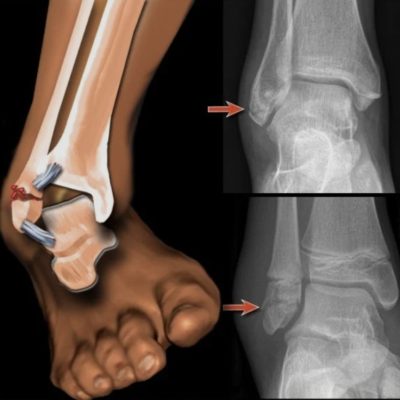

عکس شکستگی قوزک پا چگونه است؟

عکس رادیولوژی (X-Ray) همچنان اصلیترین و در دسترسترین روش تشخیص شکستگی قوزک پا است. در یک عکس استاندارد مچ پا، معمولاً سه نمای رادیوگرافی گرفته میشود تا پزشک بتواند شکستگی را از زوایای مختلف بررسی کند.

نشانههای شکستگی در عکس رادیولوژی

هنگامی که به عکس مچ پای آسیبدیده نگاه میکنید، چند علامت کلیدی نشاندهنده شکستگی است:

• خط تیره و باریک: خط شکستگی بهصورت یک خط تیرهتر از بافت اطراف در استخوان دیده میشود.

• جابجایی قطعات استخوان: اگر قطعهای از استخوان از محل اصلی خود حرکت کرده باشد.

• افزایش فاصله بین استخوانها: گشاد شدن غیرطبیعی فضای مفصل، نشانه پارگی رباط همراه با شکستگی است.

• شکستگی همراه با چرخش: استخوان نازکنی ممکن است در سطوح بالاتر نزدیک زانو دچار شکستگی شود (شکستگی Maisonneuve).